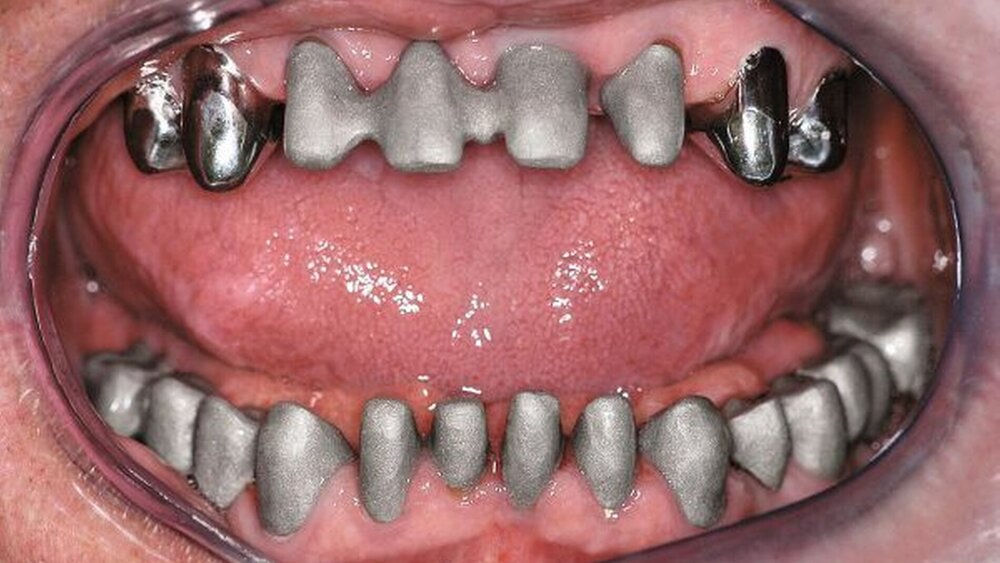

In einer weiteren Sitzung erfolgten die Gerüstanproben der angefertigten Restaurationen. Alle Provisorien im Ober- und im Unterkiefer wurden entfernt und die präparierte Zahnhartsubstanz versäubert. Danach wurde die Passgenauigkeit der hergestellten Gerüste am Patienten überprüft. Dies erfolgte unter Verwendung einer Häckchensonde sowie eines niedrigviskösen Silikons. Zudem wurden die mechanische Stabilität, die Friktion und die technische Gestaltung überprüft.

Nach durchgeführter Verblendung und Anfertigung des Sekundärgerüsts der partiellen oberen Prothese sowie Anfertigung einer separaten Wachsaufstellung wurden die Kronen und Brücken erneut anprobiert, um etwaige Änderungen die Farbe der Restaurationen betreffend vor dem Glasurbrand durchführen zu können. Zudem wurde die Sekundärkonstruktion der partiellen oberen Prothese auf ihre Passgenauigkeit hin überprüft. In einem letzten Schritt erfolgte dann die Beurteilung der Okklusion der Wachsaufstellung in Relation zu den angefertigten Kronen und Brücken.

In der darauf folgenden Sitzung wurden alle Kronen und Brücken sowie die teleskopgetragene, partielle obere Prothese für einen Zeitraum von sieben Tagen zum Probetragen mittels eines Zements auf Zinkoxid-Eugenol-Basis eingegliedert. Dem Patienten sollte durch das Probetragen der Restaurationen beziehungsweise des angefertigten Zahnersatzes die Möglichkeit gegeben werden, sowohl die Funktion beim Essen und Sprechen als auch die Ästhetik im sozialen Umfeld zu testen. Ein erneutes Entnehmen der Restaurationen wäre – für den Fall notwendiger Korrekturen – somit ohne Weiteres möglich gewesen. Da der Patient sowohl die Funktion als auch die Ästhetik betreffend keine Änderungswünsche vorbrachte und auch keine neuerlichen Beschwerden aufgetreten waren, konnten die Restaurationen nach besagtem Tragezeitraum von sieben Tagen entnommen, gesäubert und mittels eines Glasionomerzements definitiv befestigt werden. Im Anschluss wurden erneut Situationsabformungen der Kiefer genommen und der Patient erhielt nach erneutem Checkbiss-Registrat, eine okklusal adjustierte Stabilisierungsschiene im Unterkiefer. Diese dient der Therapie der beschriebenen Bruxismusproblematik und gewährleistet einen langfristen Erfolg der eingegliederten prothetischen Restaurationen (Abbildungen 13a, 13b, 13c, 14, 15a, 15b, 15c).